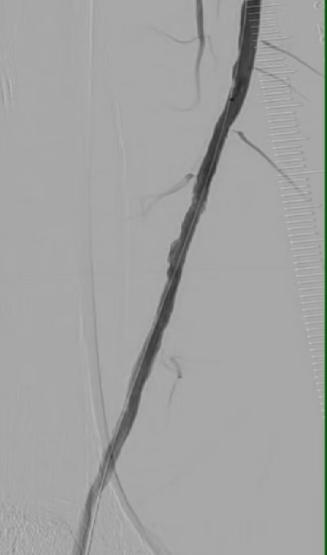

图3 术后股浅动脉下段血流通畅

在IVUS的精准导航下,赵俊来团队为患者制定了“震波球囊+药物涂层球囊”的黄金组合方案。第一步,使用震波球囊。在IVUS指引下,球囊精准定位至钙化最严重处,发出声压力波,安全地“敲松”了坚硬的内膜下钙化环。这一步如同在坚硬的冻土上松土,IVUS实时验证了钙化环已被打开,血管弹性恢复,为后续扩开血管打好了基础。第二步,使用药物涂层球囊进行充分扩张,并将抑制内膜增生的药物精准涂抹于病变处,防止血管再次狭窄。IVUS再次确认了管腔获得充分、均匀的扩张,血流通道被成功重建。

术后,蔺先生下肢的缺血症状即刻得到改善,脚趾疼痛明显缓解,在治疗复杂、钙化的外周动脉疾病时,IVUS技术帮助医生从“看得见”提升到“看得清、看得准”。未来,随着这项技术的普及,更多像蔺先生一样的患者将受益于这份血管里的“精准导航”。